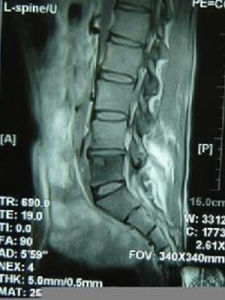

①碎片型:椎體破壞後留下小碎片,其椎旁有低密度的軟組織陰影,其中常有散在的小碎片;②溶骨型:椎體前緣或中心有溶骨性破壞區;③骨膜下型:椎體前緣有參差不齊的骨性破壞,椎旁軟組織中常可見環形或半環形鈣化影像;④局限性骨破壞型:破壞區周圍時有硬化帶(Jainr等1993)。脊椎結核CT檢查以碎片型最為常見,而脊椎腫瘤也常有與之相似之處,故應結合臨床資料綜合分析,如椎旁擴大陰影中,有鈣化灶或小骨碎片時,有助於脊椎結核的診斷。儘管如此分型,CT有時還是無法鑑別脊椎結核如脊椎腫瘤。MRI檢查具有軟組織高解析度的特點,用於顱腦和脊髓檢查優於CT,在脊椎矢面、軸面和冠面等均可掃描成像。脊椎結核MRI表現病變的椎體、間盤和附屬檔案與正常的脊椎對應處的正常信號相比,高於者為高信號,低於者為低信號。

1.椎體病變T1加權像顯示病變處為低信號,或其中雜有短T1信號。椎體病變T2加權像顯示信號增強。圖像顯示有病變椎體除信號改變外,可見椎體破壞的輪廓、椎體塌陷後順列改變和擴大的椎旁影像等。

2.椎旁膿腫脊椎結核椎旁膿腫在T1加權像顯示低信號,而T2加權像呈現較高信號。冠面能描繪出椎旁膿腫或雙側腰大肌膿腫的輪廓與範圍。

3.椎間盤改變脊椎結核X線攝片間盤變窄是早期徵象之一。MRI的T1加權像呈現低信號變窄的間盤。正常的髓核內在T2加權像有橫行的細縫隙,當有炎症時這細縫隙消失,能早期發現間盤炎症改變。

MRI在早期脊椎結核的診斷較其他任何影像學檢查包括ECT在內更為敏感。臨床症狀出現3~6個月,疑內脊椎結核病人,X線攝片無異常,MRI可顯示受累椎體及椎旁軟組織(膿腫),T1加權像為低信號,T2加權像為高信號。早期脊椎結核MRI影像可分為三型。①椎體炎症;②椎體炎症合併膿腫;③椎體炎症、膿腫合併椎間盤炎。值得提出受累椎體處於炎症期,而無軟組織和椎間盤信號改變者,不能與椎體腫瘤相鑑別,必要時應行活檢證實。